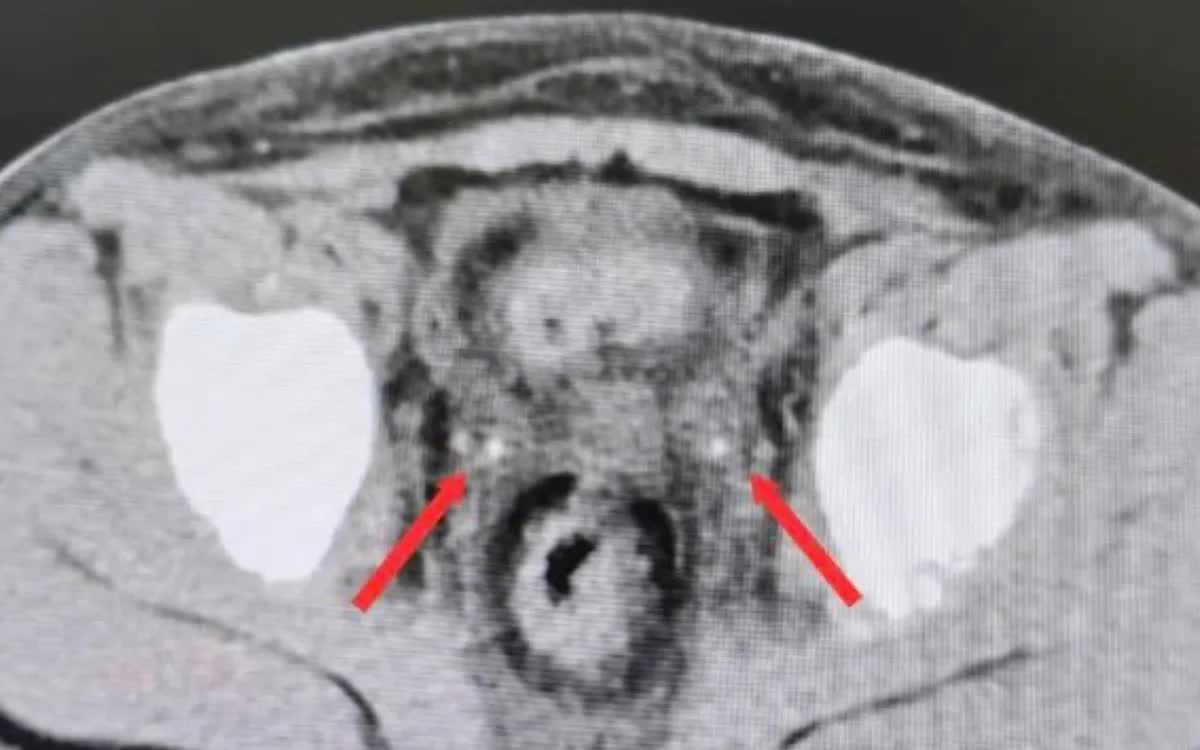

Chuyển đến Bệnh viện Nhi đồng 2 trong tình trạng không có nước tiểu, siêu âm không thấy nước tiểu trong bàng quang. Kết quả CT bụng không cản quang ghi nhận thận ứ nước hai bên, niệu quản giãn và sỏi kẹt đoạn cuối hai bên (phải 3x7mm, trái 3x20mm). Bệnh nhi được mổ cấp cứu trong đêm, nội soi bàng quang đặt ống thông JJ ngược dòng hai bên.